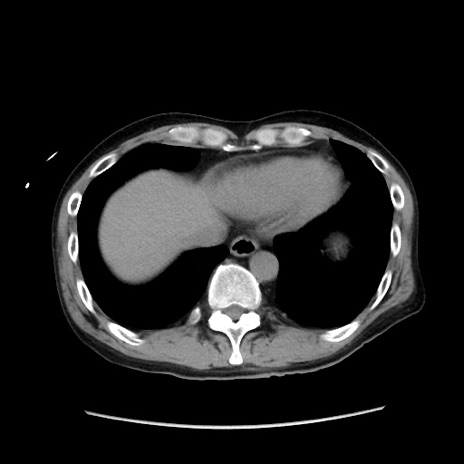

症例37(横断像)

【症例】40歳代 男性

【主訴】腹痛

【現病歴】4時間ほど前に電車に乗車中に臍部上より腹痛出現。徐々に増悪し起立困難となり、救急外来受診。生ものは数日食べていない。今朝お雑煮を食べた。

【身体所見】BT 36.8℃、BP 117/84mmHg、HR 91/min、SpO2 97%、苦悶様、腹部:臍上部広範囲圧痛あり、反跳痛±

【データ】WBC 8100、CRP 0.03